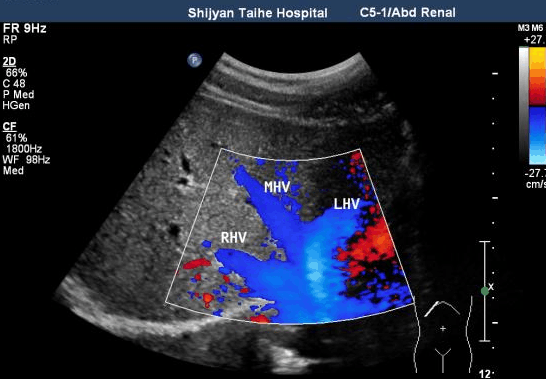

如果是肝癌高危人群,建议每6个月做一次肝脏超声检查+血清甲胎蛋白(AFP)检查,如发现可疑病灶则考虑进一步做肝脏CT或核磁共振等。

肝脏超声